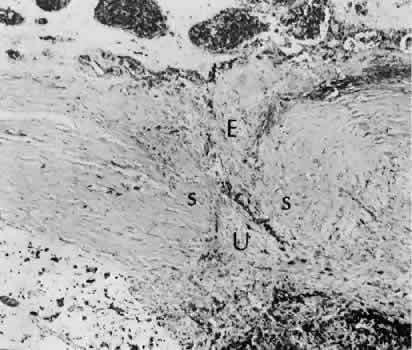

Cyclodialysis (Fig. 21) creates a cleft between the sclera and the longitudinal muscle of the ciliary body. Aqueous passes directly from the anterior chamber into the suprachoroidal space. Histologically, the longitudinal muscle of the ciliary body is disinserted from the scleral spur. Diaphanous tissue often is present in the suprachoroidal space along the route of filtration. The presence of this tissue differentiates the surgical site from artifactual disinsertion of the ciliary body, which is a common artifact of ocular tissue preparation.

Fig. 21. Light micrograph of cyclodialysis. The region of the surgical cleft between the longitudinal muscle of the ciliary body and the sclera (arrow) is filled with delicate fibrous tissue. Note the posterior location of the anterior face of the ciliary body and the angle recesses in relationship to the scleral spur (S).